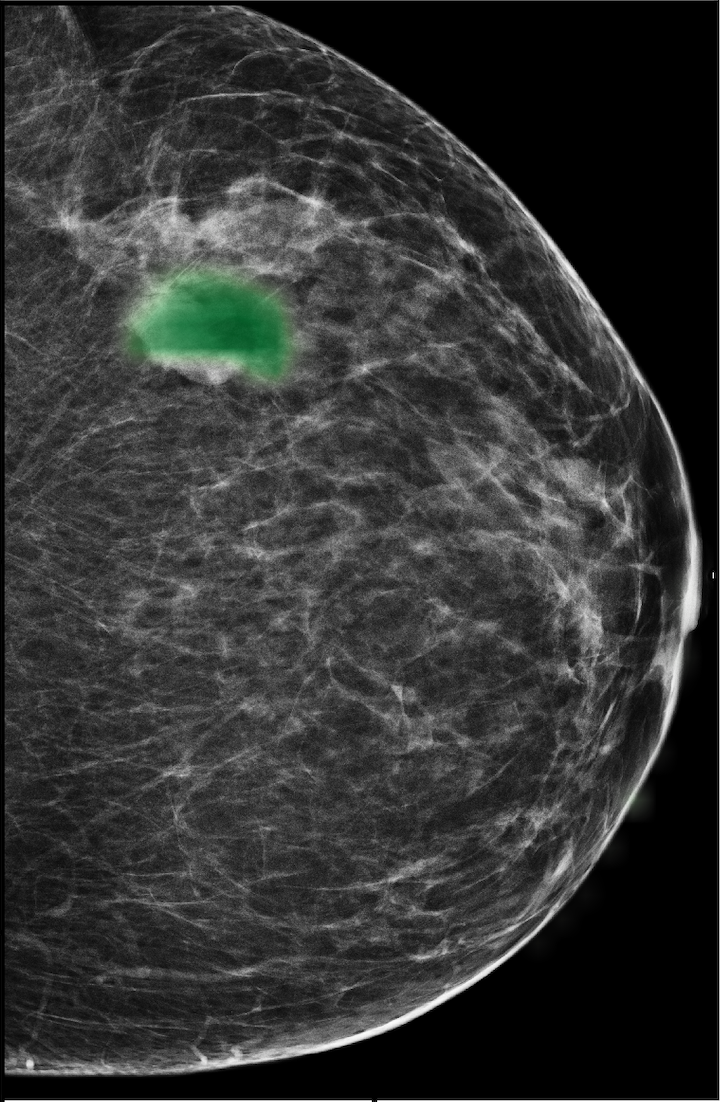

The NYU Breast Cancer Screening Dataset [78] includes 229,426 exams (1,001,093 images) from 141,472 patients.222Our retrospective study was approved by our institutional review board and was compliant with the Health Insurance Portability and Accountability Act. Informed consent was waived. Each exam contains at least four images which correspond to the four standard views used in screening mammography: R-CC (right craniocaudal), L-CC (left craniocaudal), R-MLO (right mediolateral oblique) and L-MLO (left mediolateral oblique). An example is shown in Figure 3.

For all exams matched with biopsies, we asked a group of radiologists (provided with the corresponding pathology reports) to retrospectively indicate the location of the biopsied lesions. This way we obtained the segmentation labels: where if pixel belongs to the benign/malignant findings. An example of such a segmentation is shown in Figure 3. In all experiments (except for experiments in Section 3.6 that assess the benefits of utilizing segmentation labels), segmentation labels are only used for evaluation. We found that, according to the radiologists, approximately of exams were mammographically occult, i.e., the lesions that were biopsied were not visible on mammography, even retrospectively, and were identified using other imaging modalities: ultrasound or MRI.